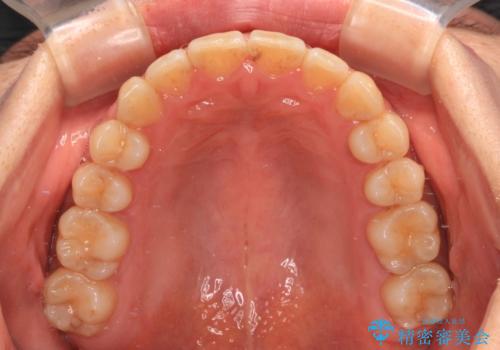

僅か1年間できれいに歯列を整えることができ、患者様には大変満足していただきました。

- 上下前歯のデコボコを気にして来院された患者様です。

叢生は軽度で、ワイヤー矯正でもマウスピース矯正でも対応可能な歯列でした。